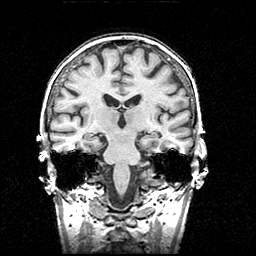

MR Study #1 -- Slice #59

[Home][Help][Clinical] Slice 59